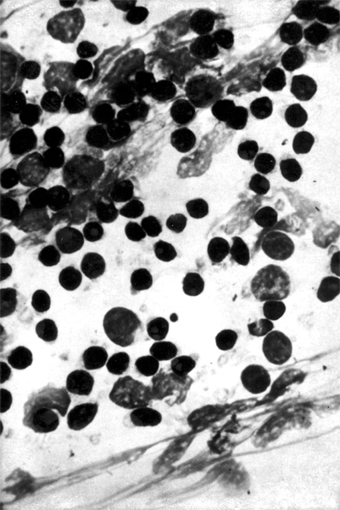

Epidemic keratoconjunctivitis is caused by adenovirus types 8, 19, 29, and 37 (subgroup D of the human adenoviruses). They can be isolated in cell culture and identified by neutralization tests. Scrapings from the conjunctiva show a primarily mononuclear inflammatory reaction (Figure 5-6); when pseudomembranes occur, neutrophils may also be prominent.

Figure 5-6: Mononuclear cell reaction in conjunctival scrapings of a patient with viral conjunctivitis caused by adenovirus type 8. (Courtesy of M Okumoto.)